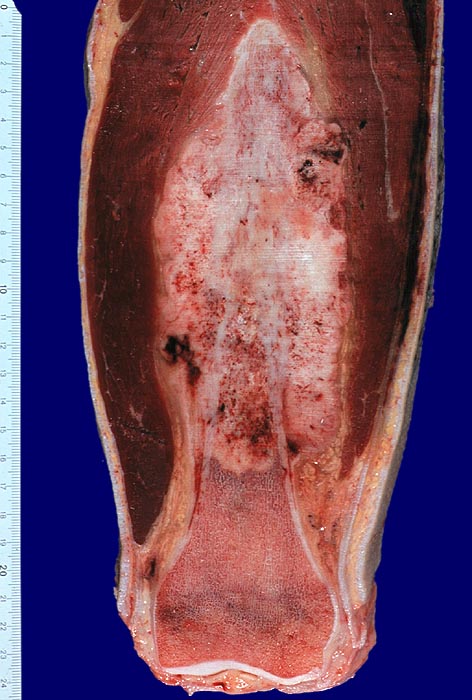

PathoPic ID 3240 - Osteosarkom

Osteosarkom

maligner Tumor

Knochen, Femur

Knochen, Knorpel, Gelenke

Tumor an klassischer Lokalisation im Bereich des distalen Femur. Das weissgraue Tumorgewebe wächst infiltrativ und destruktiv. Es füllt den Markraum und infiltriert durch den Cortex unter Abhebung des Periosts in die Weichteile.

Makroskopie

21

männlich